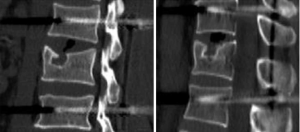

Image import: 392 horizontal images of the thoracolumbar spine in DICOM format were imported into Mimics 15.0 medical image processing software, which automatically located the images and displayed them according to the three orthogonal planes (coronal, horizontal, and sagittal), respectively (Figure 2).

Threshold segmentation: it was easy to distinguish the bones from the soft tissues based on the obvious differences in their CT values on the CT images by using the threshold segmentation method, and a mask was formed. If the gray values of adjacent pixels were close to each other and it was not easy to distinguish the boundary by the naked eye, the Draw Profile Line and the Thresholding functions in Mimics 15.0 medical image processing software were used to adjust the image threshold to 462–2,676 HU, so that the boundaries of the thoracolumbar vertebral body, intervertebral disc, sacrum, and facet joint were clearer (Figure 3).